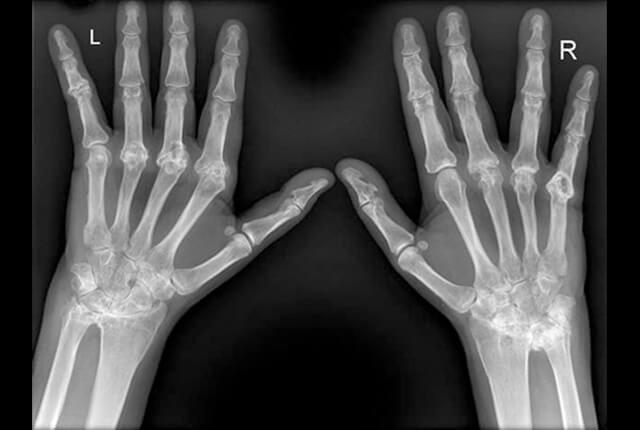

• 単純X線:骨びらん、関節破壊

単純X線